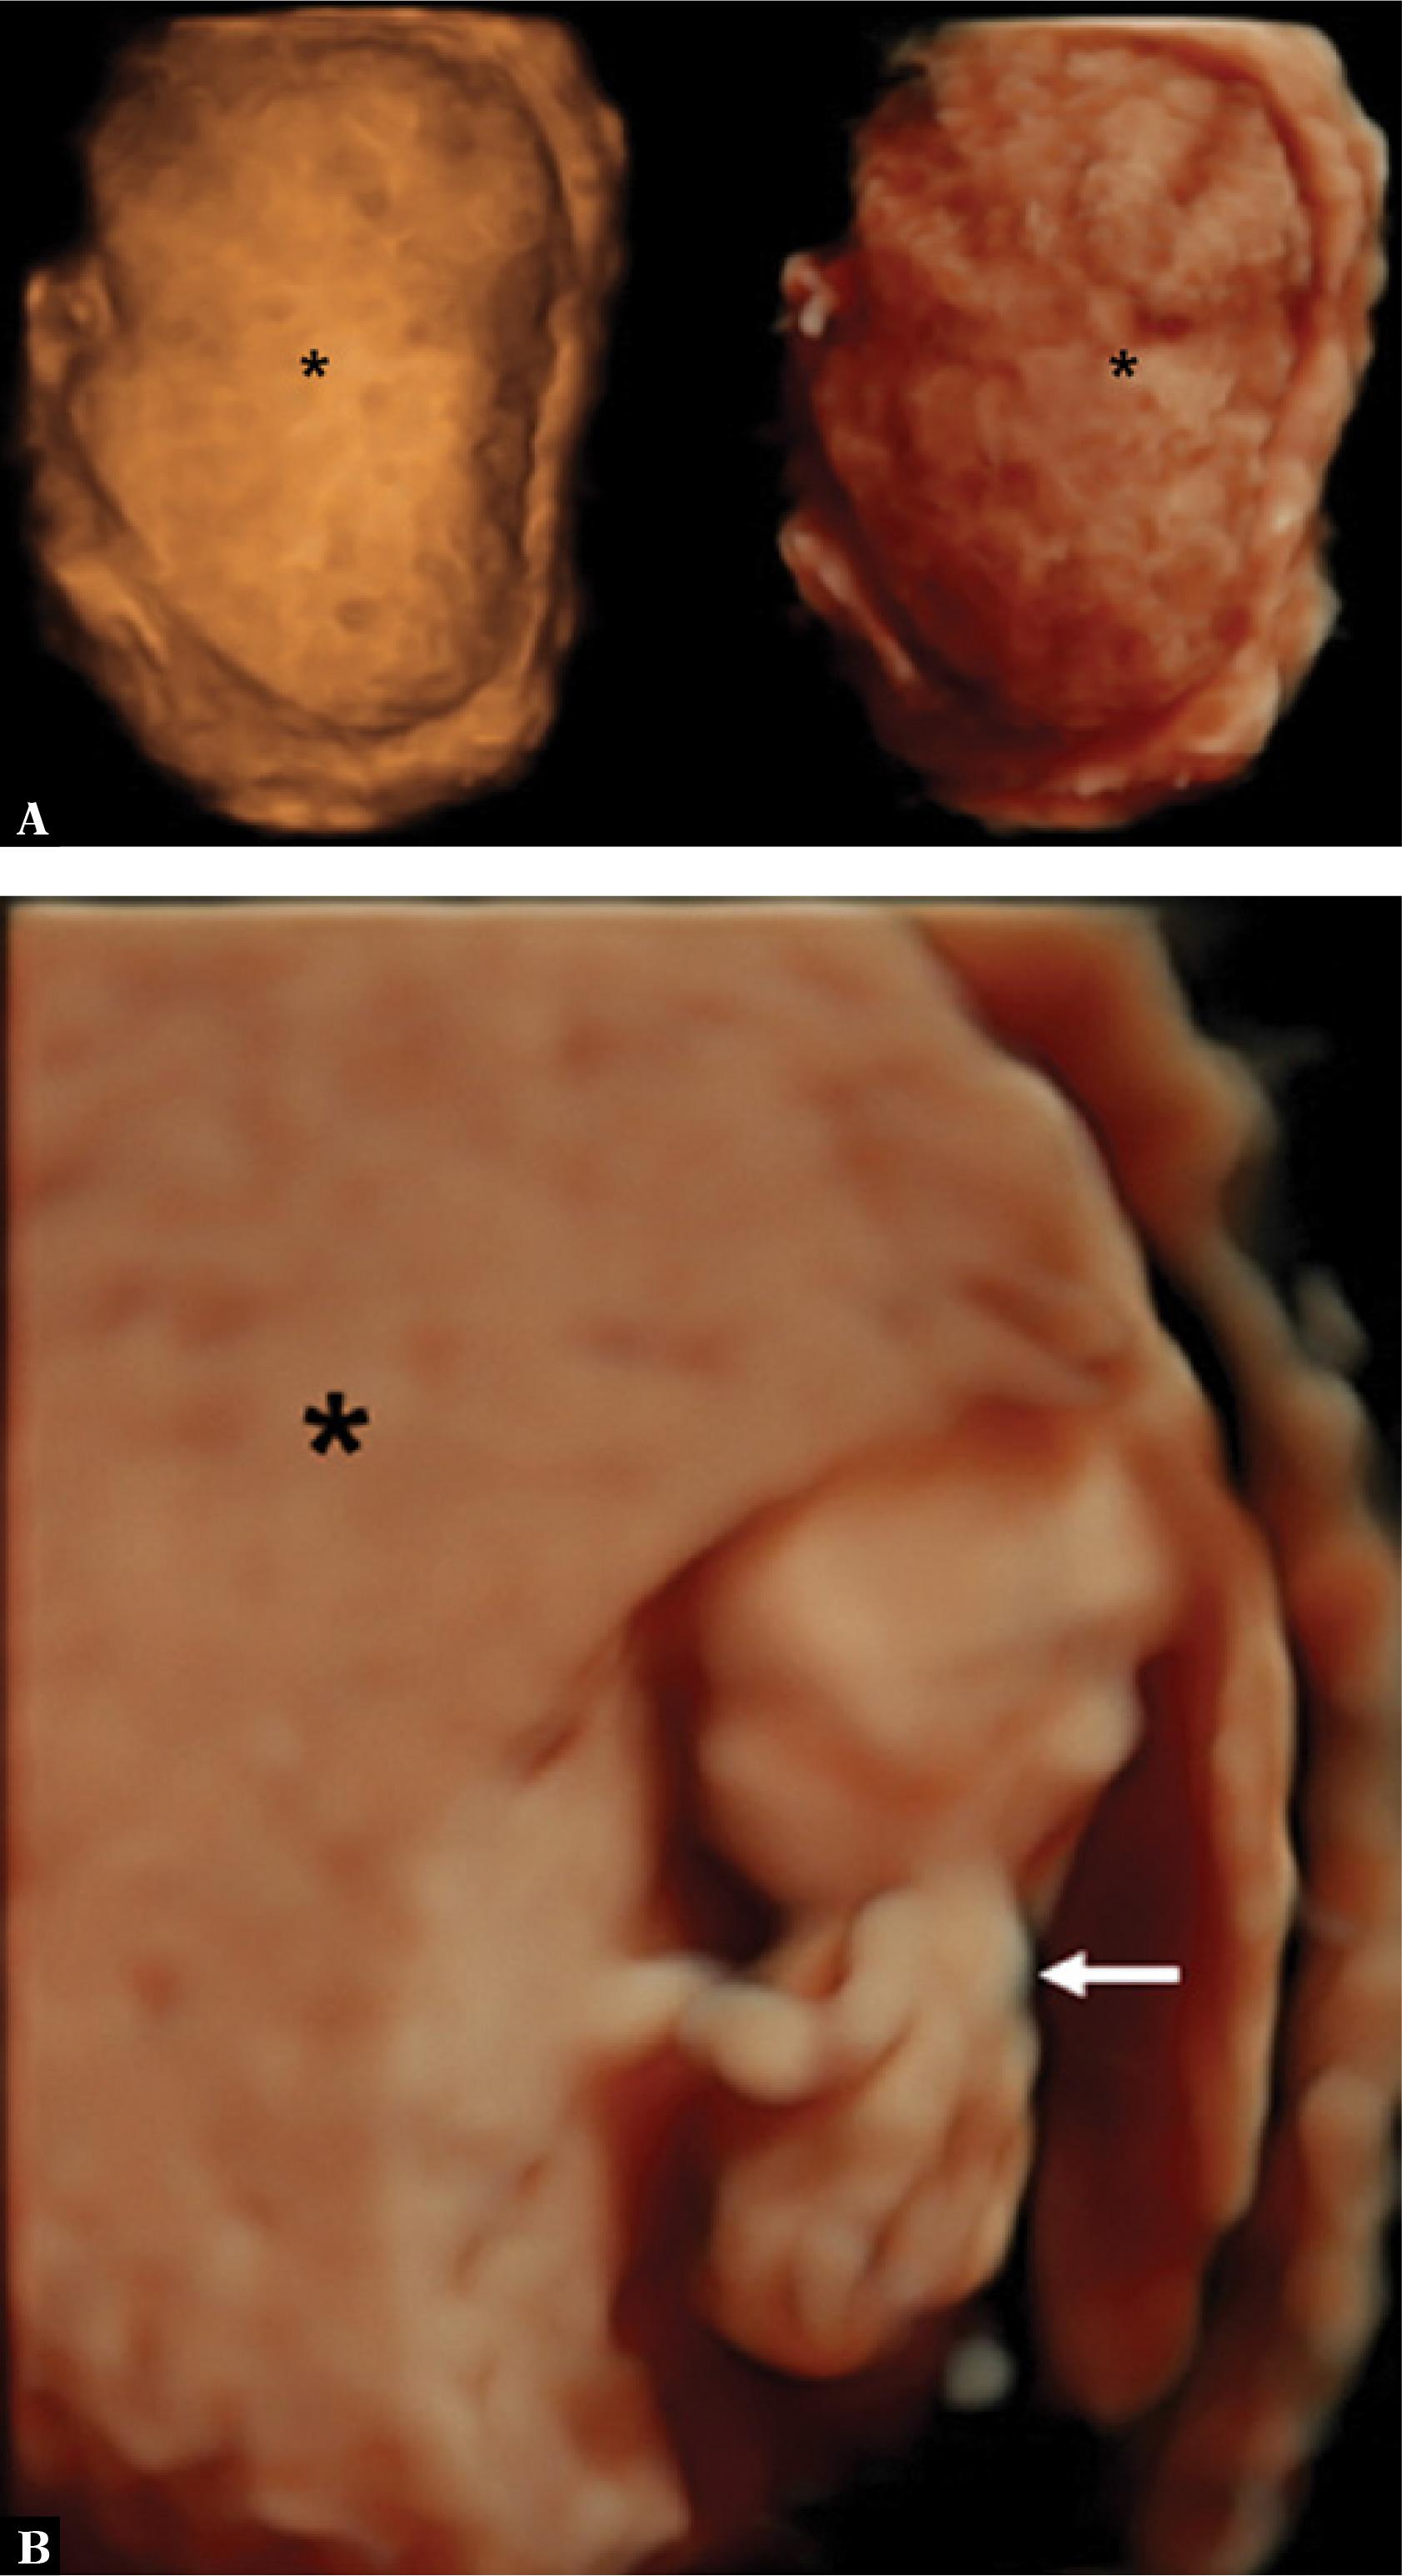

Fig. 2